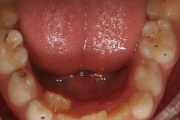

Keel

Vali sind huvitav pilt ja me näitame sellega seotud haigust ja sümptomeid